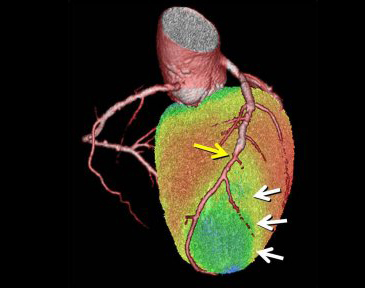

近年、心筋SPECTと心臓CTの融合画像により虚血性心疾患の包括的な診断が行われるようになってきています。本院では2007年7月より融合画像作成ソフトウェアを導入し一般臨床に用いています(図3)。

これにより冠動脈病変の部位と心筋虚血の関係をとらえ、適切な治療法の決定に役立てています。図4は労作性狭心症の症例です。ステントを留置した既往があり、最近になって再び狭心症症状が出てきました。左冠動脈前下行枝におけるステント留置部の遠位に狭窄病変がみられ、これが狭心症の原因となっている病変であることが分かります。

図4a 心臓CT

図4b SPECT/CT融合画像